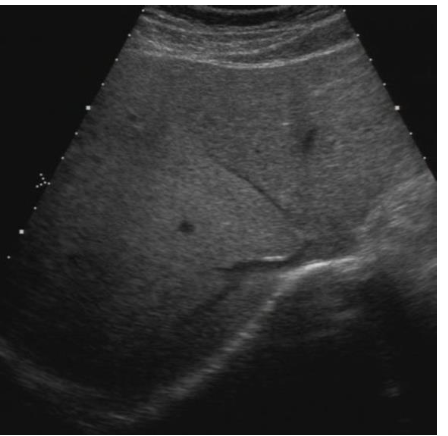

what echotexture is shown?

heterogenous

homogenous